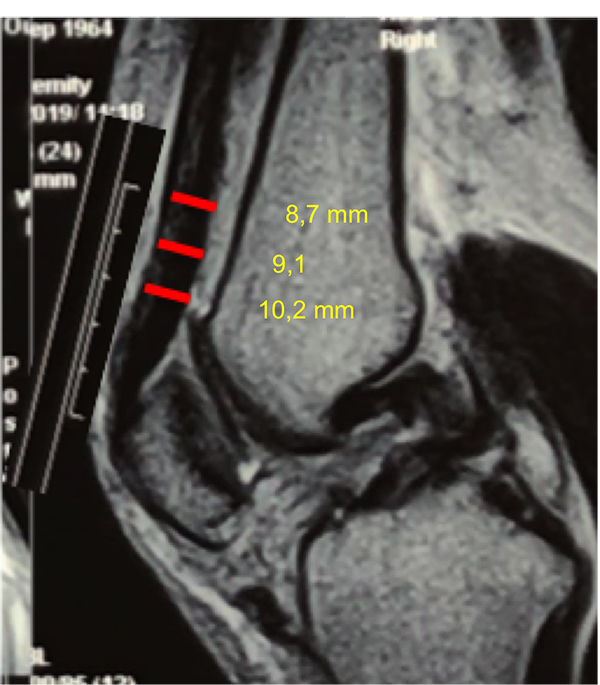

A los tres meses del accidente, una vez rehabilitadas las fracturas expuestas en mano y pie izquierdo, la rodilla presentó un examen físico compatible con secuela de lesión inestable de ligamento colateral interno con bostezo grado II (++/+++) con tope laxo en 30° de flexión y en extensión completa. No presentó derrame articular. Se observó desplazamiento posterior de tibia estructurado. Cajón posterior grado III (sin tope neto) y Godfrey positivo. Lachman positivo con pivot shift positivo. Rango de movilidad completo sin bloqueo. Dolor en compartimiento interno tercio posterior. El score de Lysholm Tegner preoperatorio de 10 y 1 respectivamente. El estudio por resonancia magnética (RM) confirmó el diagnóstico (figs. 1 y 2). El espesor medido del tendón cuadricipital a 30, 40 y 50 mm de inserción proximal en rótula por este estudio en cortes sagitales fue de 10.2 – 9.1 – 8.7 mm, respectivamente (fig. 3).

Figura 3: Corte sagital de RM. Medición de espesor de tendón a 30, 40 y 50 mm de inserción en rótula.